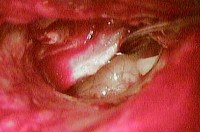

Отоскопия и микроотоскопия проводятся после туалета наружного уха с тщательным очищением наружного слухового прохода. Они выявляют наличие перфорации в барабанной перепонке. Причем хронический гнойный средний отит, протекающий по типу мезотимпанита, отличается наличием перфорации в натянутой области барабанной перепонки, в то время как для эпитимпанита типично расположение перфорации в ненатянутой области.

Хронический гнойный средний отит имеет 2 клинические формы: мезотимпанит и эпитимпанит. Мезотимпанит (туботимпанальный отит) составляет около 55% и отличается развитием воспалительного процесса в пределах слизистой оболочки барабанной полости без вовлечения ее костных образований. На долю эпитимпанита (эпитимпано-антрального отита) приходятся остальные 45% случаев хронического гнойного среднего отита. Он сопровождается деструктивными процессами в костной ткани и во многих случаях ведет к образованию холестеатомы уха.